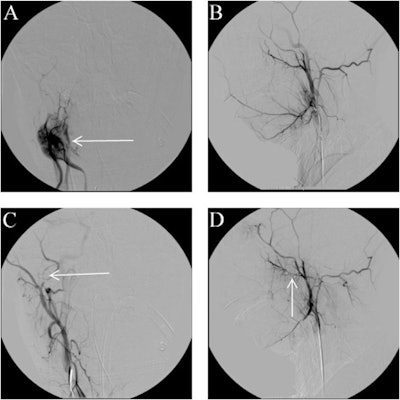

At this point, clinicians consulted with interventional imaging specialists who performed an angiography of her right external carotid artery under general anesthesia, according to the report.

The imaging showed contrast extravasation and a pseudoaneurysm emerging from her inferior alveolar branch of the right internal maxillary artery.

The team placed a rapid transit microcatheter over a guidewire into the right maxillary artery, and a series of detachable coils were deployed across the inferior alveolar artery. After the procedure, the girl was transferred to the neurosurgical intensive care unit for continued observation.